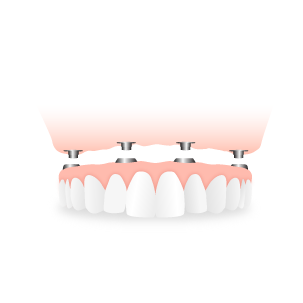

ALL ON 4

All on 4 predstavlja krunice postavljene na ugradjena samo 4 implanta po vilici.